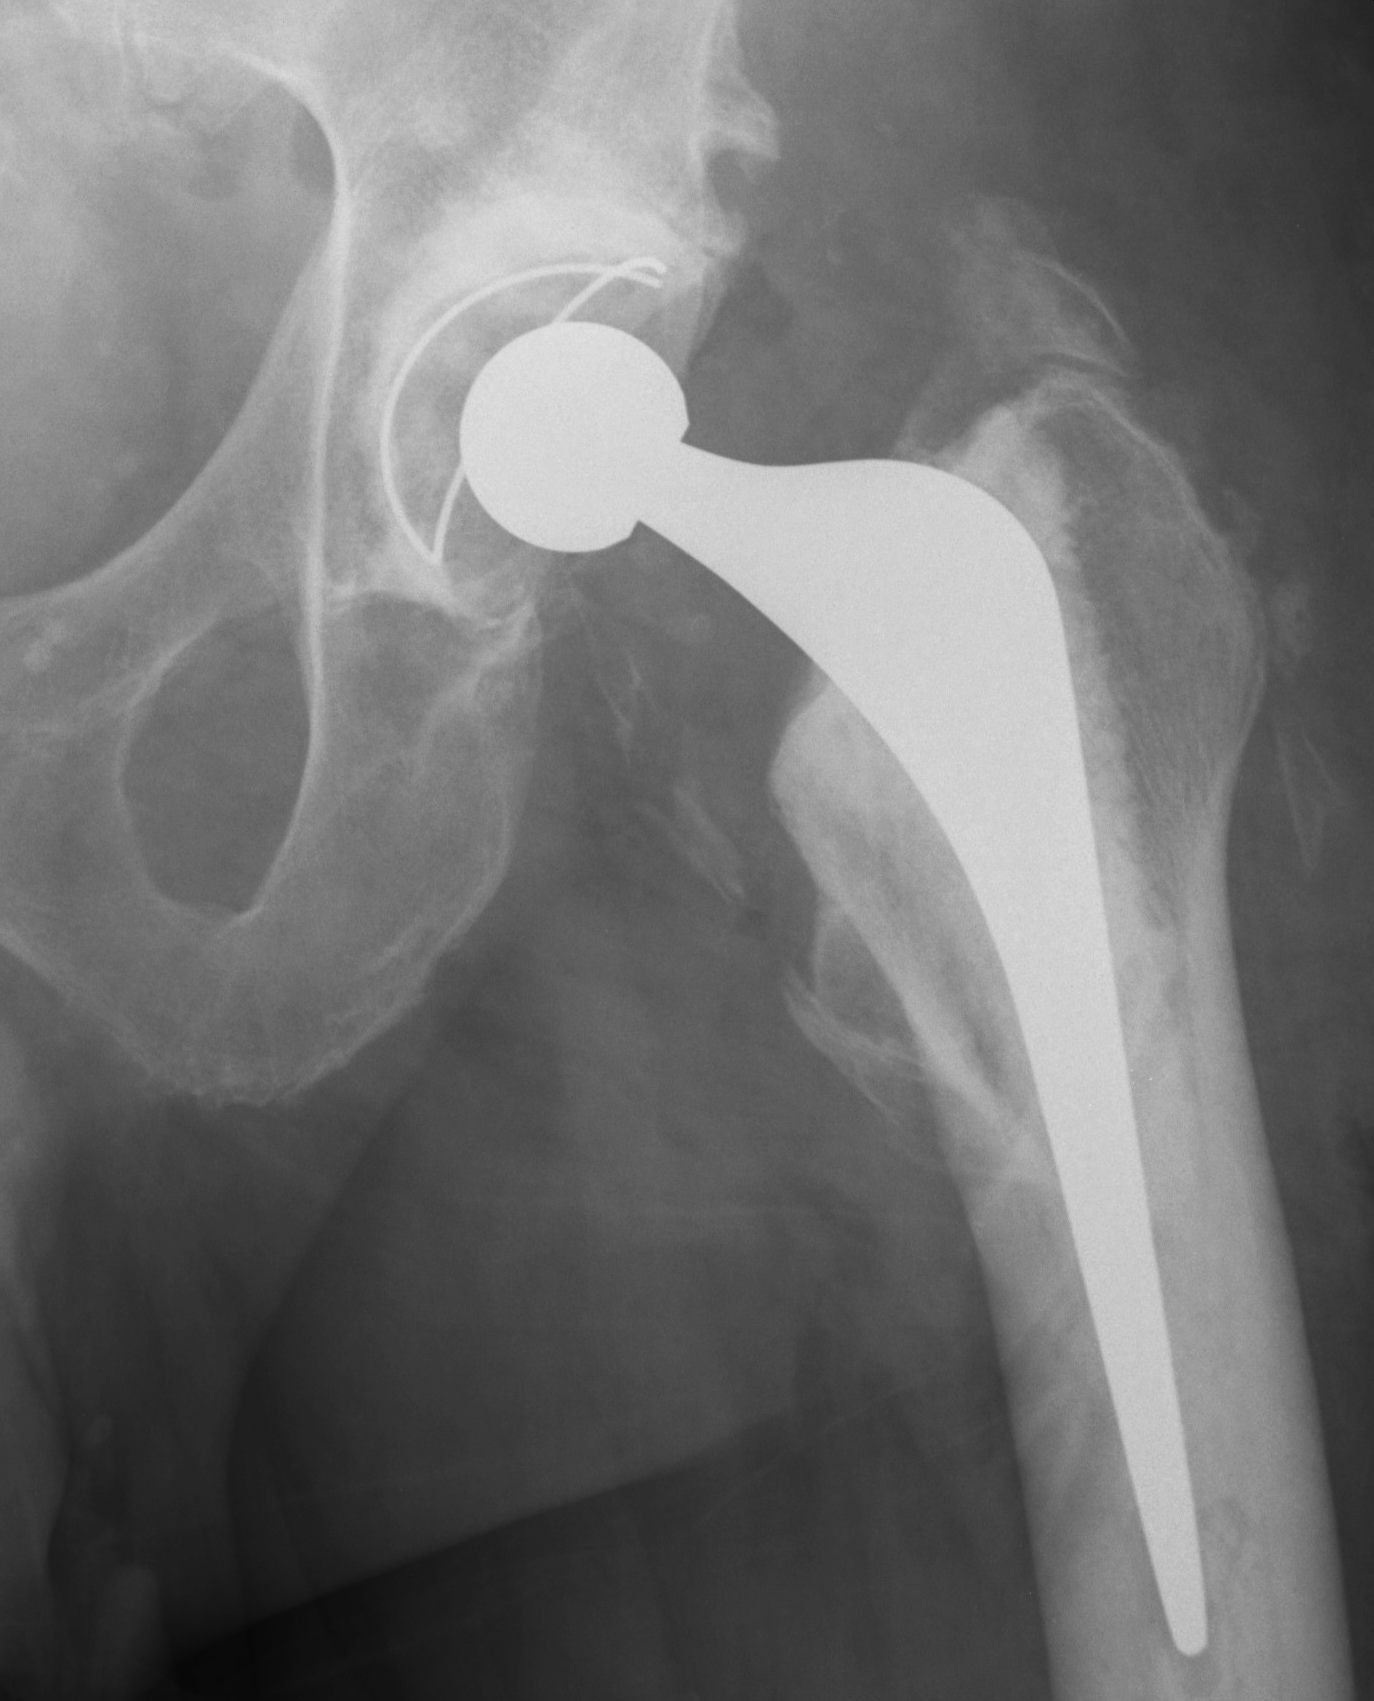

Brooker Classification: Type III and Type IV clinically relevant

Type I: Isolated islands of bone

Type II: Bony spurs from pelvis and proximal femur, gap > 1 cm

Type III: Gap < 1 cm

Type IV: Apparent ankylosis